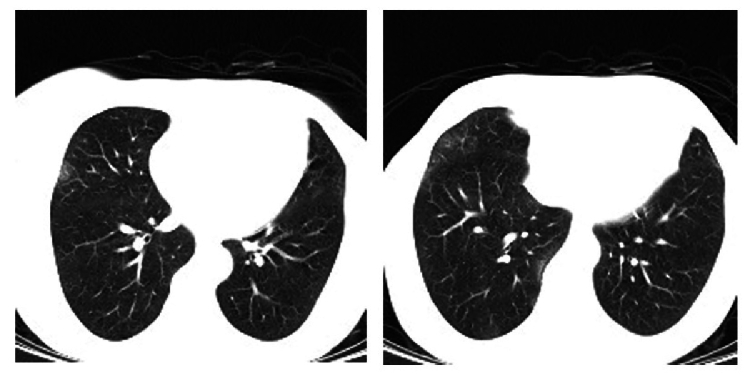

Case report: A 58-year-old female presented to our emergency department with sudden unilateral visual loss following a recent hospitalization for viral meningoencephalitis. Magnetic resonance imaging (MRI), cerebrospinal fluid (CSF) analysis, polymerase chain reaction (PCR) of the aqueous humor, reverse transcription polymerase chain reaction (RT-PCR) of the nasopharyngeal swab specimen, chest computed tomography (CT), and fundus photography were performed for the patient. Ophthalmic examination revealed severe ocular inflammation and yellowish patches of necrotizing retinitis in the right eye, compatible with the diagnosis of ARN. The result of aqueous humor PCR was positive for varicella zoster virus (VZV). The patient received a single intravitreal ganciclovir injection and 10 days of intravenous ganciclovir, followed by oral acyclovir. The patient underwent COVID-19 screening tests: while the chest CT scan showed features highly suggestive of COVID-19, the RT-PCR was negative on two occasions. Two months later, best-corrected visual acuity improved to 20/70 in the right eye, the anterior chamber reaction and keratic precipitates resolved, and the vitreous haze decreased significantly.